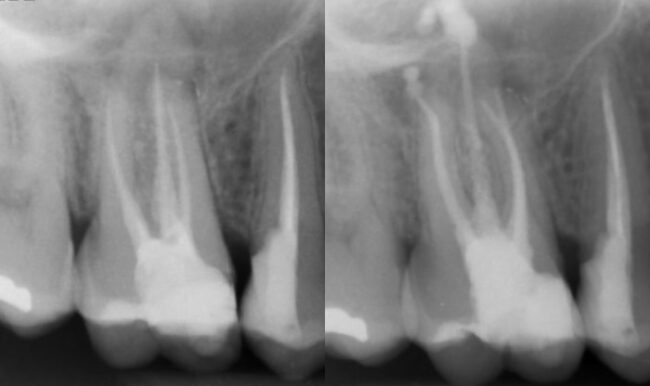

El Dr. Rubén Monge nos muestra en este caso un paciente con absceso apical severo en 1.6 con un tratamiento de conducto realizado previamente. En el retratamiento utiliza RetreatAll® para eliminar la gutapercha y BlueShaper® para la instrumentación.